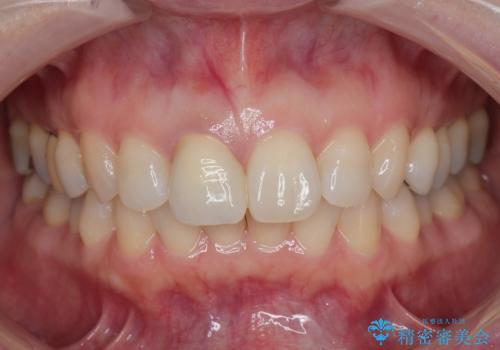

- ジルコニアクラウンスペシャル・仮歯 16.5万円 精密根管治療(リトリートメント)・ファイバーコア 12.1万円費用は治療当時の料金となります

問題なく綺麗な被せ物が入りました。

保険の被せ物は安価ですが劣化しやすいため着色しやすい素材です。

セラミックの素材は劣化することなくまた虫歯の再発のリスクも下げてくれます。